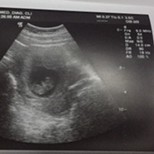

Nakita ba agad ang heartbeat ni baby sa unang ultrasound niya?

yes, 9weeks po 174hb nya 🥰

164 hb nya with good cardiac

Yup. TransV sa 7 weeks! 🤗